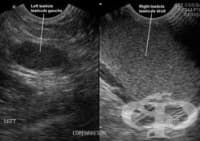

Мамографията е най-разпространеният метод за диагностика на млечните жлези. Представлява рентгенов м...